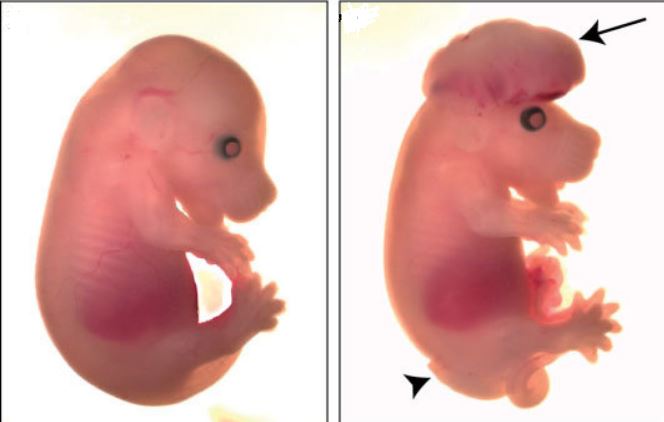

Research on mice, rats, rabbits and other laboratory animals

- Create and induce a variety of animal models

The many similarities between animals and humans, the short lifespan of animals and the determining of the studied factors in an appropriate period of time, as well as the possibility of controlling the experimental conditions are some of the advantages of using animals in clinical research.